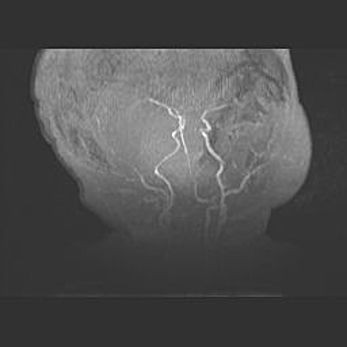

Мальформация Денди-Уокера. Киста задней черепной ямки.

Агенезия мозолистого тела.

Возраст: 2,5 месяца

Вес: 2420 г

Пол: женский

Окружность головы: 37 см

Срок гестации: 32 недели

Мальформация Денди—Уокера — редкий вид патологии ЦНС, представляющий собой врожденный порок развития каудального отдела ствола и червя мозжечка, ведущий к неполному раскрытию срединной (Мажанди) и латеральных (Лушка) апертур IV желудочка мозга. Для этогно синдрома характерна триада симптомов: гипотрофия червя мозжечка и/или полушарий мозжечка, кисты задней черепной ямки, гидроцефалия различной степени. В 70% случаев порок сочетается и с другими аномалиями головного мозга, в частности с агенезией мозолистого тела.